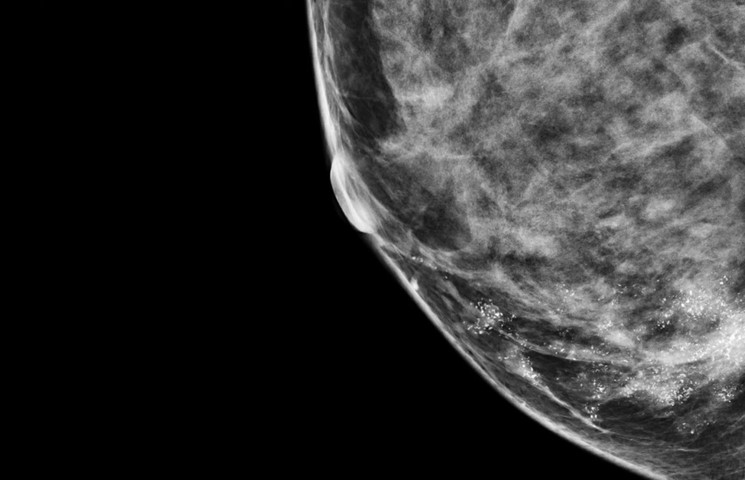

Theo Polyak, nghiên cứu này có thể giúp chia các quý bà, quý cô thành hai nhóm: nhóm có nguy cơ cao và nhóm có nguy cơ thấp mắc ung thư vú. Điều này rất quan trọng, vì những quý bà, quý cô có nguy cơ cao cần được tầm soát, chụp nhũ ảnh (mammograms) và làm thêm các xét nghiệm khác thường xuyên hơn để sớm phát hiện bệnh. Bà cho biết thêm: “Nghiên cứu này chỉ mới là bước khởi đầu. Càng hiểu biết nhiều, chúng ta càng có thể dự đoán chính xác nguy cơ mắc bệnh.”